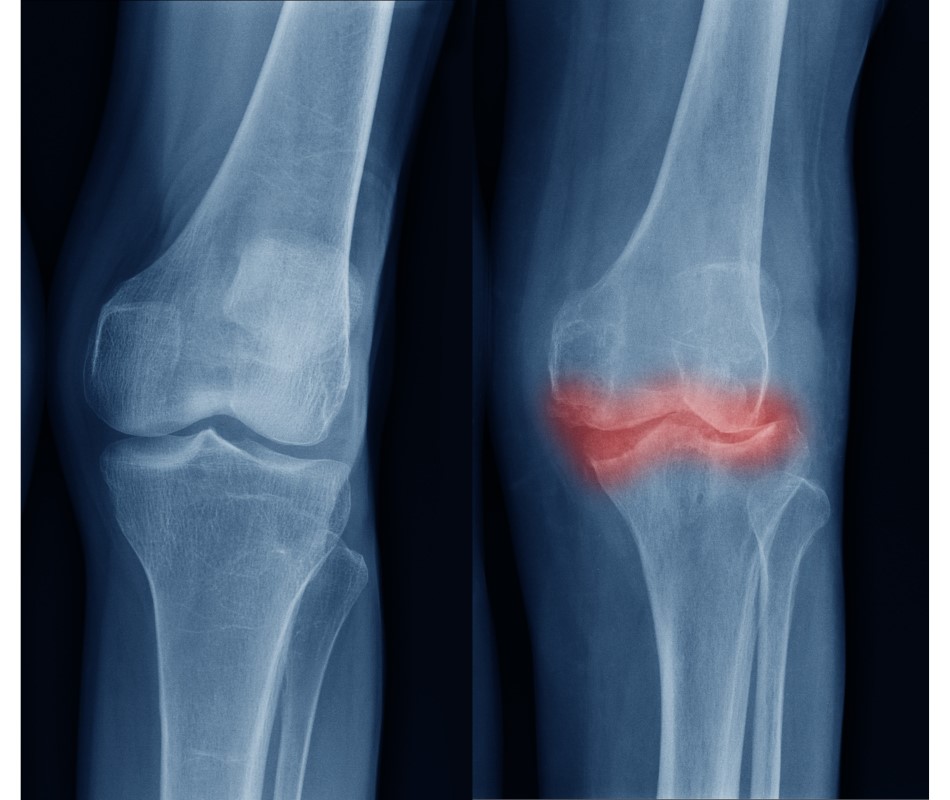

膝の痛みが続くと現れる症状が変形です。

図の✕印は膝の痛みの多い代表的な部位ですが、ここは腱や靱帯です。これらがつながる筋肉によって上に引かれて付け根の腱や靱帯が緊張し、次第に痛んできます。

この痛みを取るために腱や靱帯の緊張を取ることが痛みを取る最善の方法です。